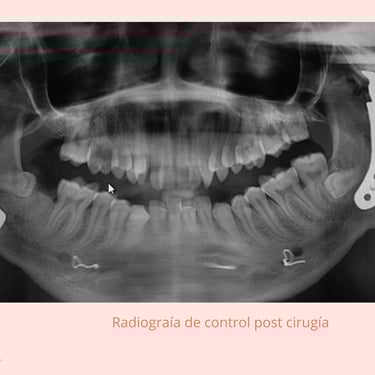

Cirugía (si es necesario): Procedimientos quirúrgicos para liberar la articulación y restaurar la función.

Diagnóstico de anquilosis en la ATM, permitiendo la planificación de un tratamiento adecuado.